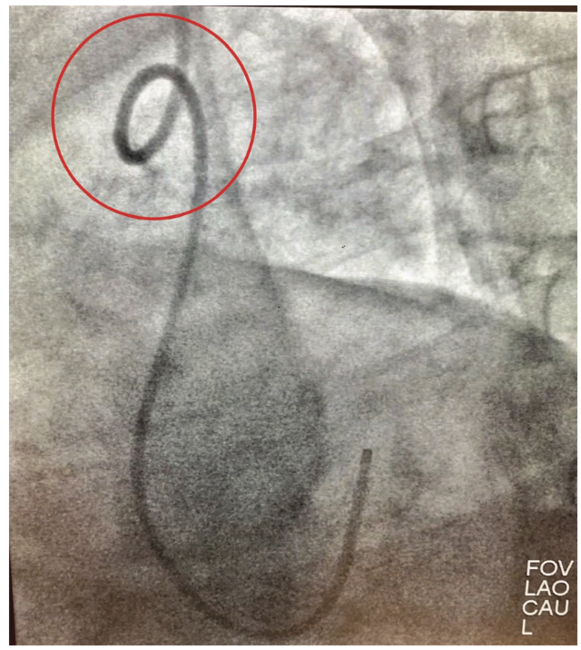

Unfortunately, the technologist would need to be close to the radiation source in order to help the patient, as well as have both hands in the primary radiation beam. After convening, we decided to attempt this technique with the use of minimal intermittent fluoroscopy and proper radiation protection. Regrettably, we did not have lead gloves available (which may or may not help with shielding, being in the primary beam). Under fluoroscopy, the kink was moved to the distal brachial artery very carefully while confirming the patient did not have pain in the arm. Once the catheter reached the distal brachial artery, under fluoroscopy, the technologist compressed the brachial artery with significant pressure proximal to the kink (Figures 3-4). The attending physician un-torqued and simultaneously pulled the catheter (Figure 5). Within seconds, we resolved the issue safely and efficiently. We aborted the RRA access site, cannulated the left distal radial artery (Figure 6), and completed the case.